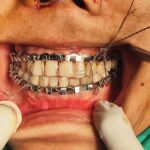

A 24 year old female patient reported to the department of Oral and Maxillofacial Surgery (OMFS) Supercare Hospital Shillong with Chief complain of severe pain in Bilateral TMJ and progressive development of open Bite. Her MRI of the condyle showed condylar hypoplasia with degeneration of the articular disc and reduced joint space.

The team of Oral and Maxillofacial Surgeons (who are a part of the OncomaxNE association) headed by Dr.Bobby L Majaw from Shillong and Dr. Ashutosh Vatsyayan from Guwahati carried out what is possibly the first ever CAD/CAM (Computer-aided – design/Computer-aided Manufacturing ) Alloplastic Bilateral Temporomandibular Joint replacement in a private set up in North East at Supercare Hospital, Shillong.

The patient post-surgery had no pain in her TMJ and was able to open and close her mouth properly.